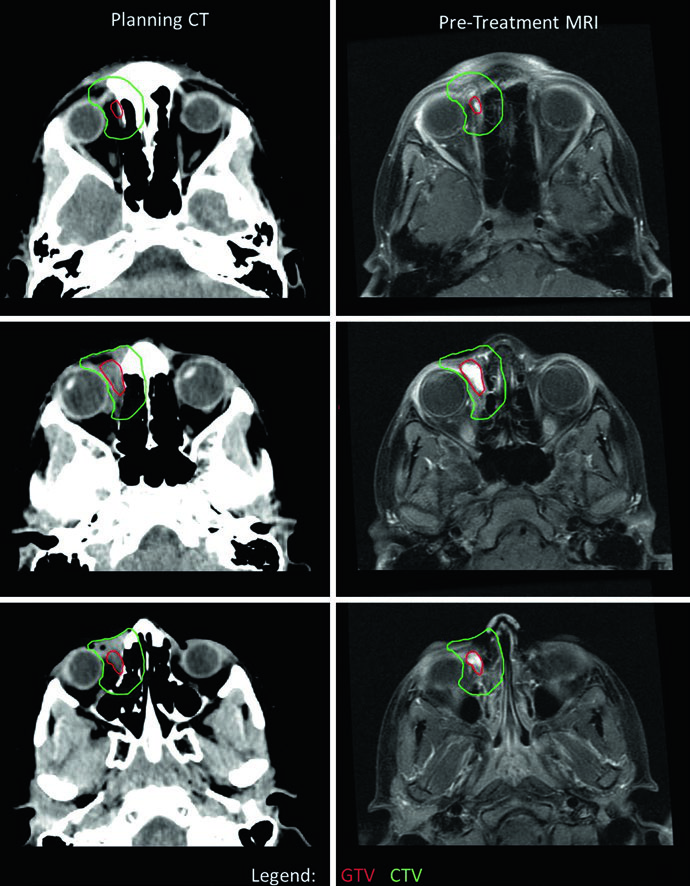

No RMS orbital, o delineamento exige atenção à preservação de estruturas oculares. Neste caso, a CTV se estendeu além da órbita óssea em alguns cortes por suspeita de erosão óssea — em geral, o CTV de RMS orbital não deve exceder os limites da órbita óssea na ausência de erosão. Um desvio lateral do olho direito foi utilizado para otimizar a preservação do cristalino e do nervo óptico. Como o tumor respondeu minimamente à quimioterapia de indução, optou-se por dose única de 50,4 Gy. Se houvesse resposta, seriam utilizados dois níveis: 36 Gy com cone-down para 50,4 Gy. Para comparação com tumores benignos e malignos do SNC que também exigem planejamento cuidadoso ao redor de estruturas oculares, consulte nosso artigo sobre tumores malignos do SNC.